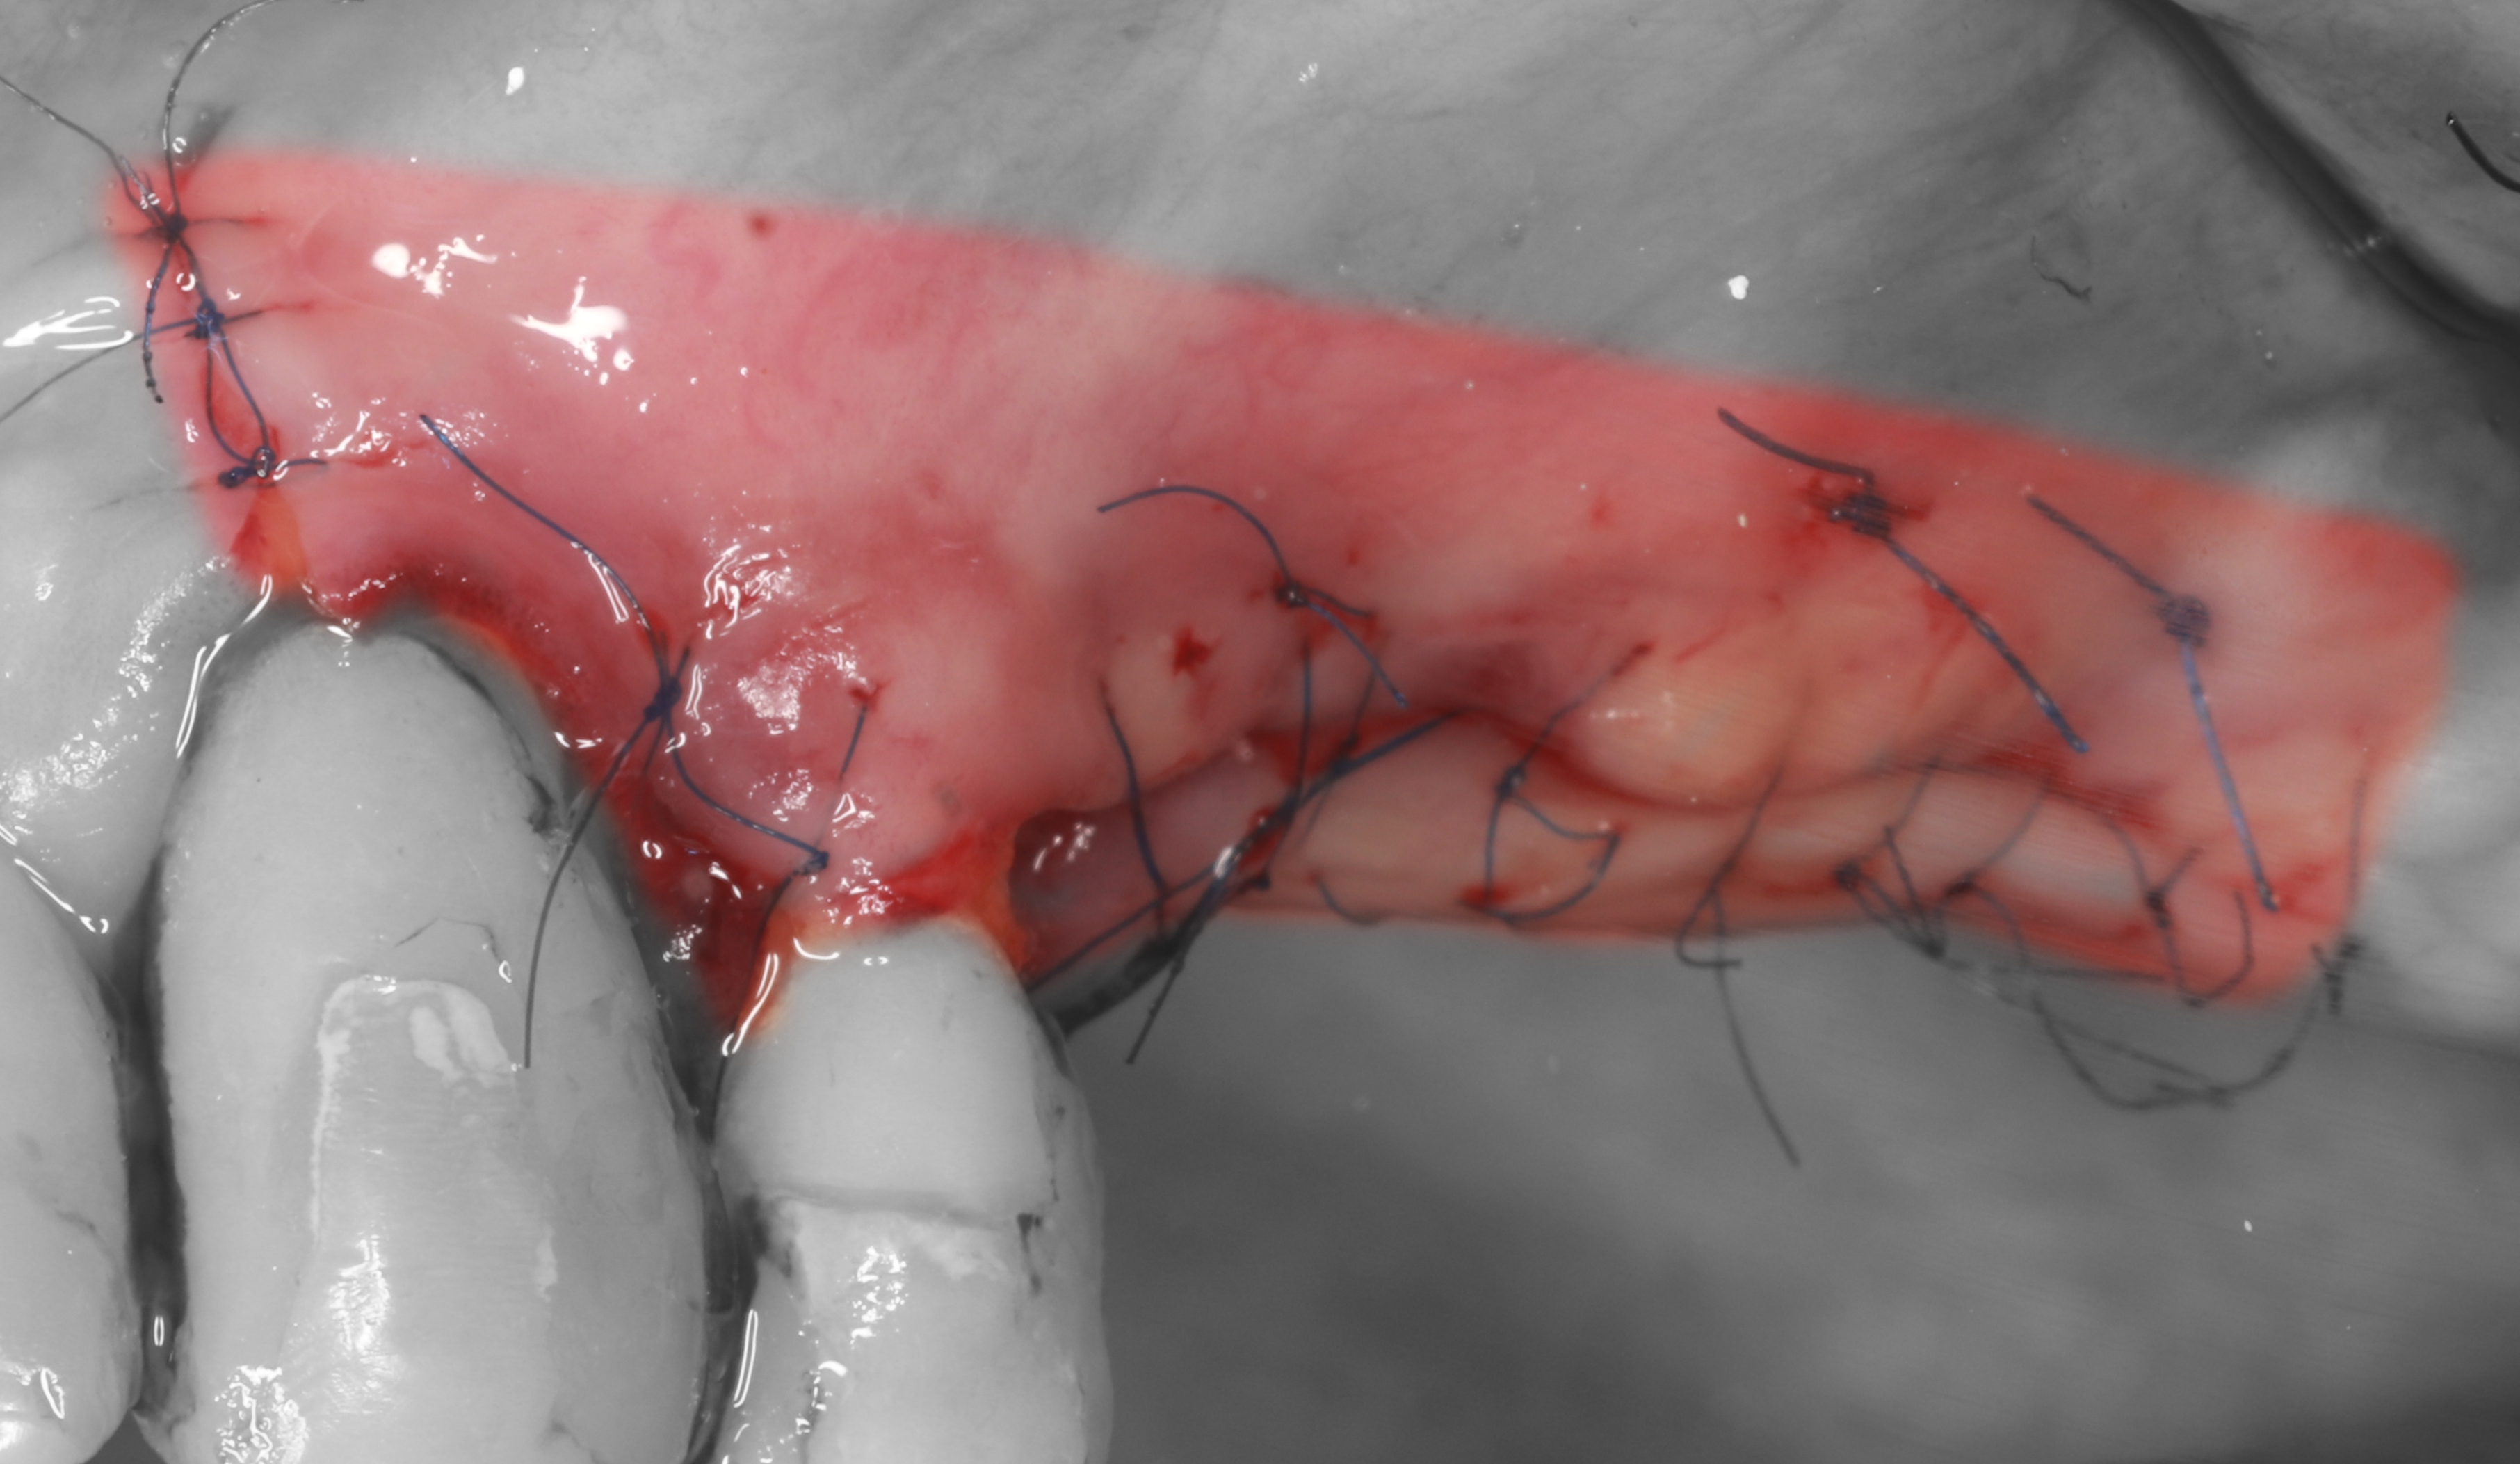

11) Коллагеновая мембрана прижата к лоскуту с помощью надкостничного матрасного шва.

12) Наложены швы полипропилен 6/0, 7/0.